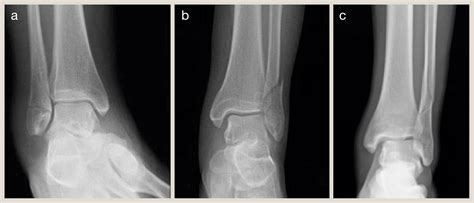

Diagnosing a Fracture Weber C involves a thorough clinical examination and imaging studies. The diagnostic process typically includes:

• Clinical Examination: Assessing the patient's pain, swelling, and range of motion. Checking for tenderness and deformity around the ankle joint.

• Imaging Studies: X-rays are the primary imaging modality used to visualize the fracture. Additional imaging, such as CT scans or MRIs, may be required to assess the extent of the injury and plan treatment.

X-rays are essential for determining the exact location and severity of the fracture. A lateral view of the ankle can help identify the level of the fibular fracture in relation to the syndesmosis. CT scans provide detailed images of the bone structure and can help in surgical planning. MRIs are useful for evaluating soft tissue injuries, such as ligament damage.